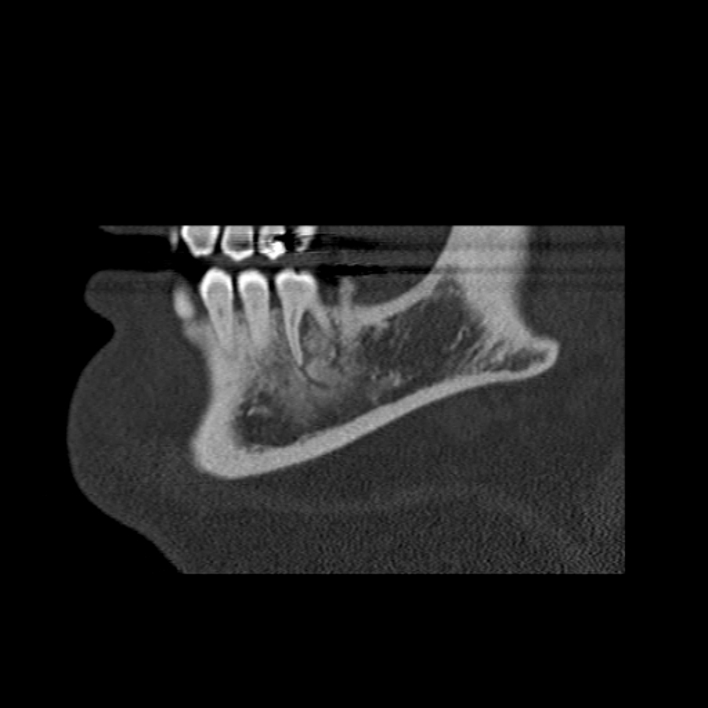

Figure 1 for case Chondroblastic osteosarcoma of the mandible

Figure 1